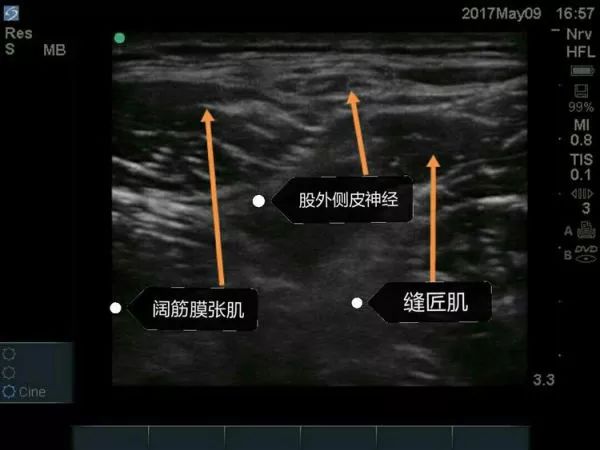

超声下股外侧皮神经阻滞要点

①适应证: 髋部手术的术后镇痛,感觉异常性股痛,大腿近端外侧肌肉活检。

②探头的位置: 横向放置,紧贴髂前上棘的下方,缝匠肌SaM的外侧缘。

③目标: 局麻药在阔筋膜张肌TFL和缝匠肌之间扩展。

④局麻药: 5-10ml。

超声引导下股外侧皮神经阻滞技术为骨科髋关节手术切口提供理想术后镇痛效果。